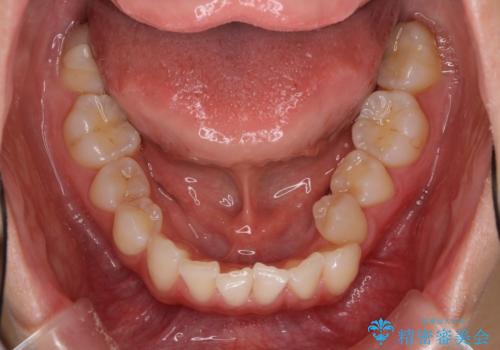

上顎前歯が2本欠損 インビザラインによる叢生の解消

- 深い咬み合わせと前歯のデコボコを気にして来院された患者様です。

上顎前歯2本が欠損しているため、妥協的なゴールを設定しインビザラインで矯正治療を行うこととしました。

上下前歯の大きさのアンバランスにより、深い咬み合わせと奥歯の咬みにくさがなかなか解決されず、治療に長期間を要することとなりました。